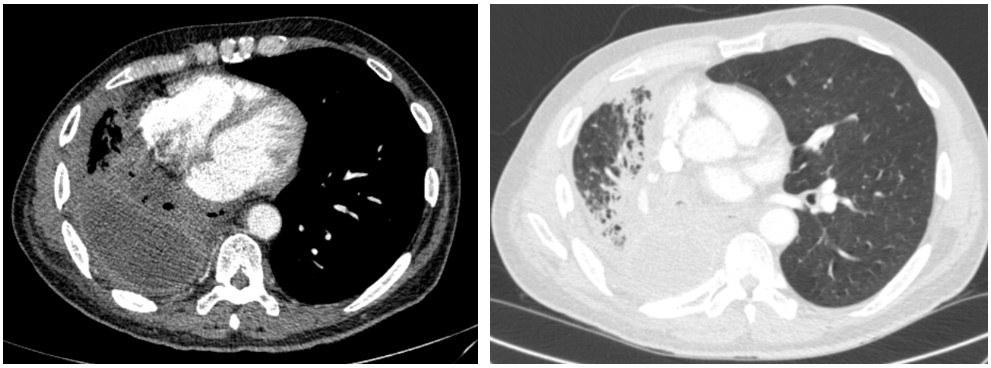

On evaluation, he was tachycardic with fever (38.6 °C) and exhibited decreased air entry to his RLL. Contrast enhanced Computed Tomography (CT) of the chest was done and showed right middle and lower lobe consolidation with areas of cavitation and a moderate right sided pleural effusion (Image 1). The patient was started on broad spectrum antibiotics. A repeat CT chest was obtained on day 7 due to clinical deterioration, which showed a new right-sided hydropneumothorax (Image 2). A pigtail chest tube was placed by Interventional Radiology that drained brown, markedly turbid fluid that was exudative based on Light’s criteria (pH < 6.3, LDH 575). His chest tube output continued to drain copious volume (average: 400 ml/day) of turbid, foul-smelling fluid with particulate matter over the next few days. Microbiological data identified polymicrobial growth of oral/upper respiratory tract: GPC in pairs and chains, GPRs, and candida glabrata. Subsequent CT chest after chest tube placement is shown below (Image 3):